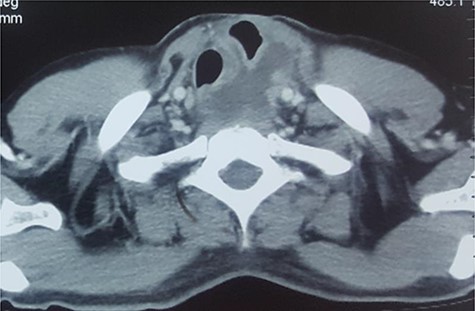

After unremarkable 18 months of the second surgery, he presented with a few days’ history of fever, dysphagia and a painful swelling in the left neck. There was an erythematous, hot cystic swelling measuring 6 cm × 5 cm in the neck underlying the earlier incision. Ultrasound of the neck revealed a loculated collection with some debris, without significant cervical lymphadenopathy. A contrast esophagram was performed which showed an intact esophagogastric continuity without obstruction, stricture, dilatation, leakage or delayed gastric emptying. A CECT scan revealed a distended blind-ended native esophagus filled with high-density fluid extending from neck to the diaphragmatic hiatus (Figs 1 and 2).

CECT of the chest. Note the huge pyocele posteriorly and the gastric conduit anteriorly.